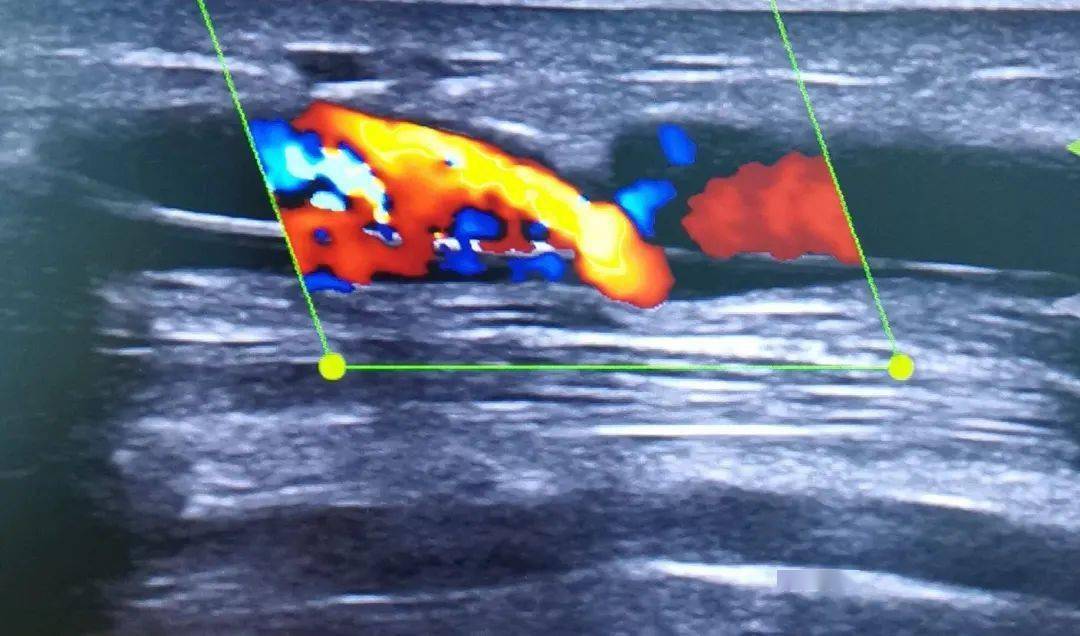

下肢深静脉血栓导致动静脉瘘?